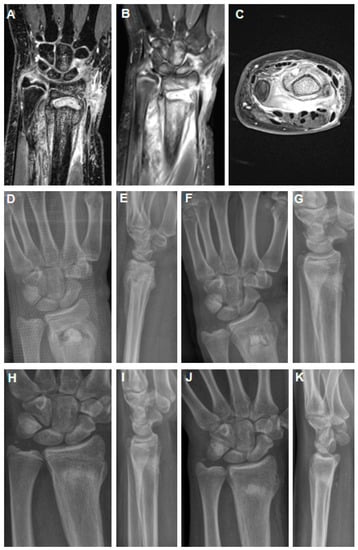

Figure 2. MRI imaging 4 weeks after K-wire removal after initial closed reduction and K-wire fixation of a dislocated distal radius fracture in an 11-year-old girl (AC). Abscess formation in the distal metaphysis of the radius with intensive periosteal reaction (A,B) and affection of the growth through the K-wire channel. Axial section revealed strong abscess into the palmar soft tissues (C). Post-operative X-rays show filling of the metaphyseal defect area with a PMMA spacer (D,E). The spacer was exchanged against a hydroxyapatite–calcium sulphate biomaterial 9 weeks after stage 1 (F,G). After 6 weeks, there was already good remodeling of the metaphyseal bone zone (H,I). At midterm follow-up of 16 months, there was correct alignment of the wrist joint with premature closure of the growth plate (J,K).

She was seen 5 weeks after K-wire removal in our emergency department for a swollen and redness wound at the distal radius. MRI imaging revealed consolidation of the fracture with good alignment of the distal radius and clear abscess formation in the distal radius with extensive periosteal and palmar soft tissue involvement. Affection of the epiphyseal plate by the former K-wire channel was also suggested.

Similarly to case 1, a two-stage protocol was applied with debridement and removal of the abscess from the metaphyseal distal radius and the surrounding soft tissue. A palmar modified Henry approach as well as a dorsal incision were performed to evacuate the abscess formation. A PMMA spacer loaded with gentamicin, clindamycin, and vancomycin was placed (mixture: 40 g Copal®, Heraeus, Wehrheim, Germany + 2 g vancomycin powder). Approximately 3 cc of the antibiotic-loaded PMMA was used.

Nine weeks later, stage 2 was performed with removal of the PMMA spacer and the bone defect was filled with three pellets of a hydroxyapatite–calcium sulphate biomaterial loaded with vancomycin (PerOssal®, Osartis GmbH, Dieburg, Germany). Perioperatively, the patient received a single shot of 2 g cefazolin. Pain-adapted full weight-bearing was allowed, but a restriction of sport activity involving any contact was given for eight weeks. There was no recurrence of infection and the X-rays showed complete bone defect healing with incorporation of the biomaterial into the metaphyseal area of the distal radius. There was also premature closure of the epiphyseal plate at the last follow-up after 16 months. Range of motion was extension/flexion 70-0-80° with pro-/supination: 80-0-80°.